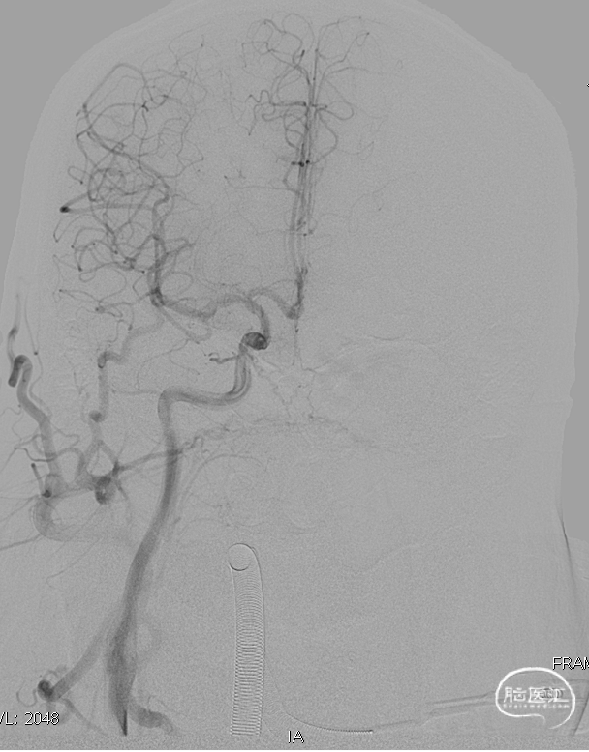

术后造影见瘘口不显影。

术前

术后

术后右侧颈总造影,未见向瘘口供血。